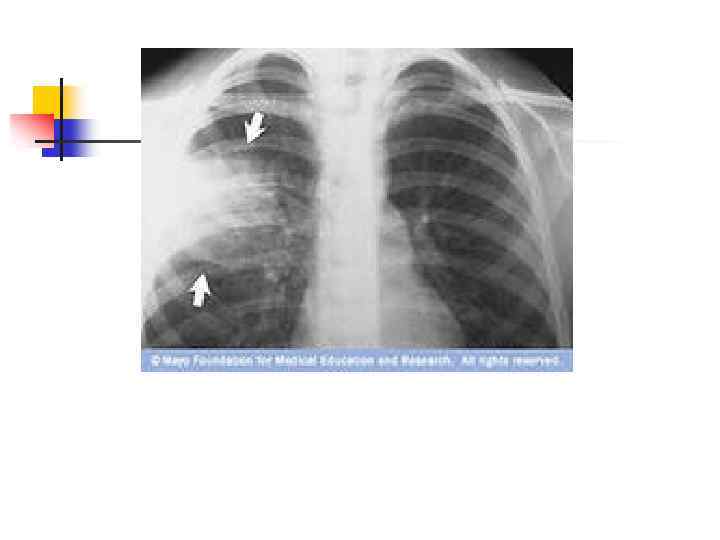

Общий анализ мокроты – слизисто – гнойная , содержит много лейкоцитов. n Бактериологическое исследование мокроты. n Рентгенография лёгких – очаг(и) затемнения 1 – 2 см в диаметре. n